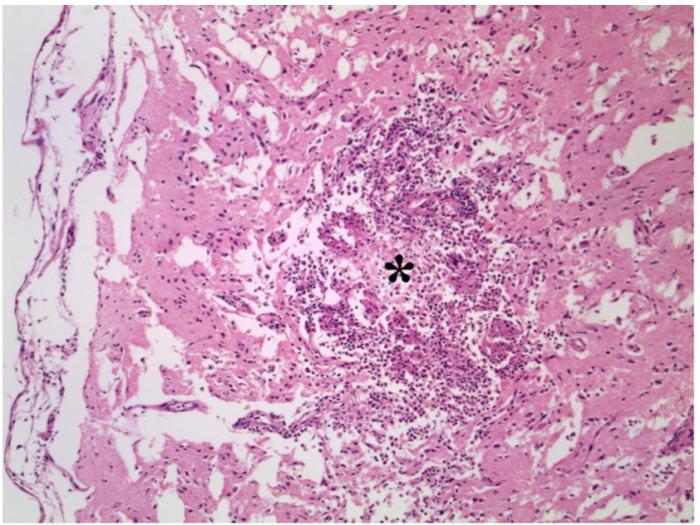

- Citología esplénica (PAAF): inflamación mixta con abundantes hifas fúngicas, tanto extracelulares como intracelulares (macrófagos) (Figura 2).

Estudio post mortem

- Hepatitis granulomatosa con abundantes hifas fúngicas pigmentadas (Figura 3).

- Encefalitis granulomatosa necrotizante multifocal con hifas intralesionales (Figura 4).

Los cultivos fúngicos fueron negativos, pero la morfología histológica fue altamente compatible con feohifomicosis.

Desde el punto de vista citológico e histológico, se observan hifas septadas, de morfología irregular y diámetro variable, con paredes celulares pigmentadas como característica distintiva. En ocasiones puede emplearse la tinción de Fontana-Masson para confirmar la presencia de melanina. El diagnóstico definitivo requiere aislamiento mediante cultivo y/o técnicas moleculares como PCR, aunque pueden obtenerse resultados negativos incluso en casos confirmados histológicamente1.